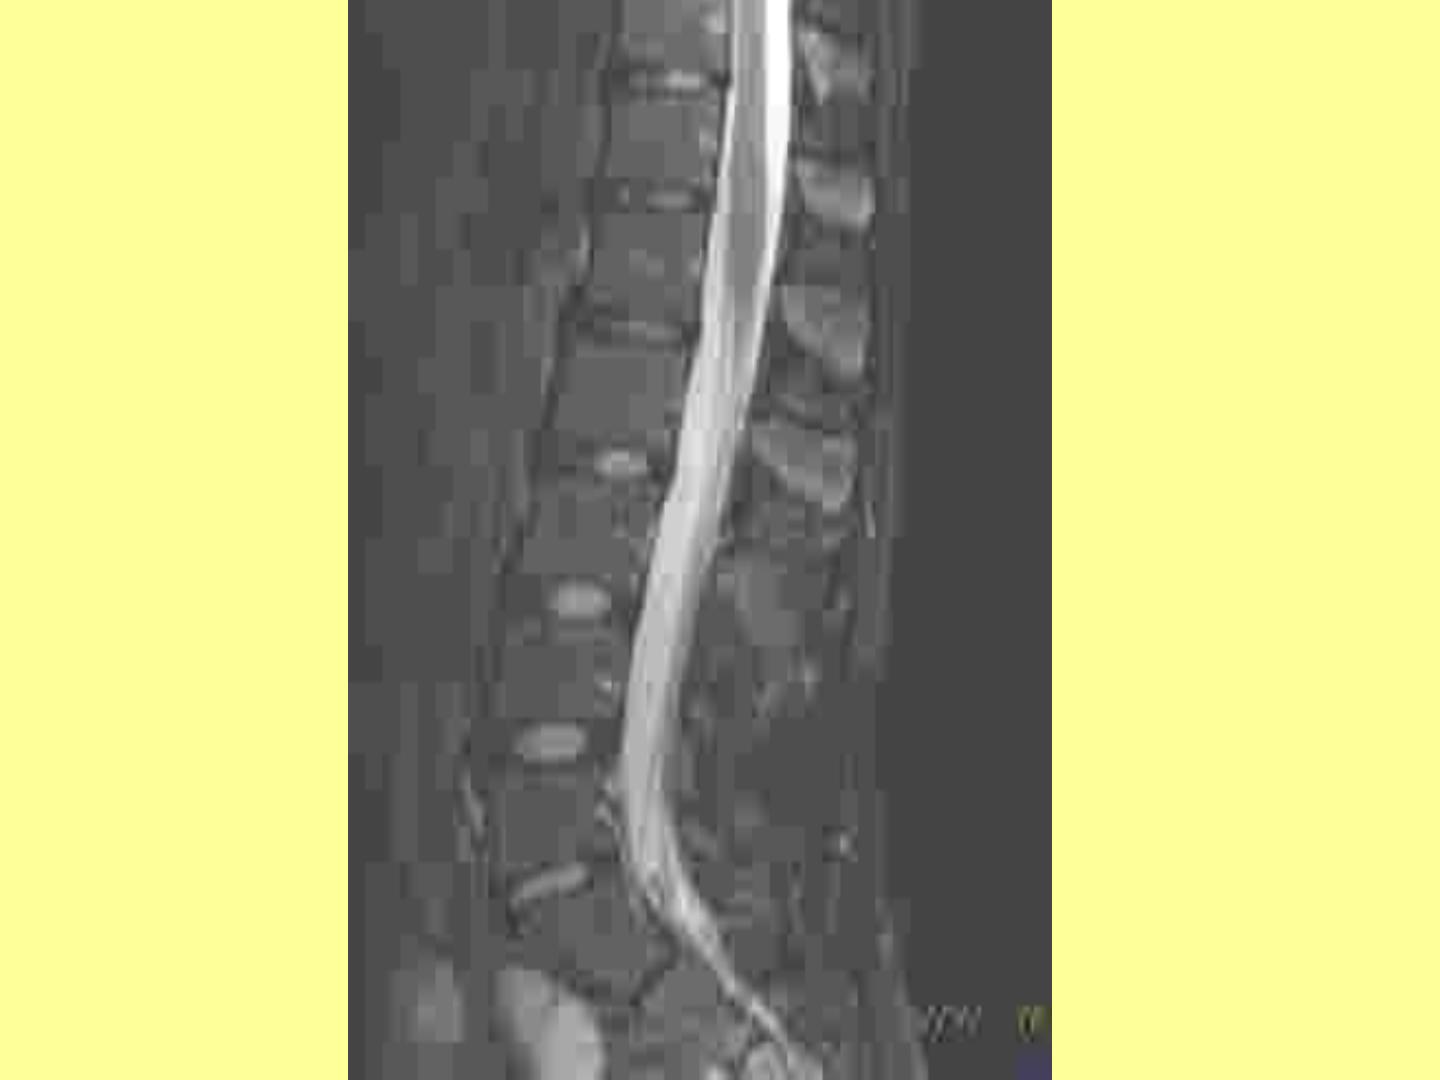

QUEUE DE CHEVAL